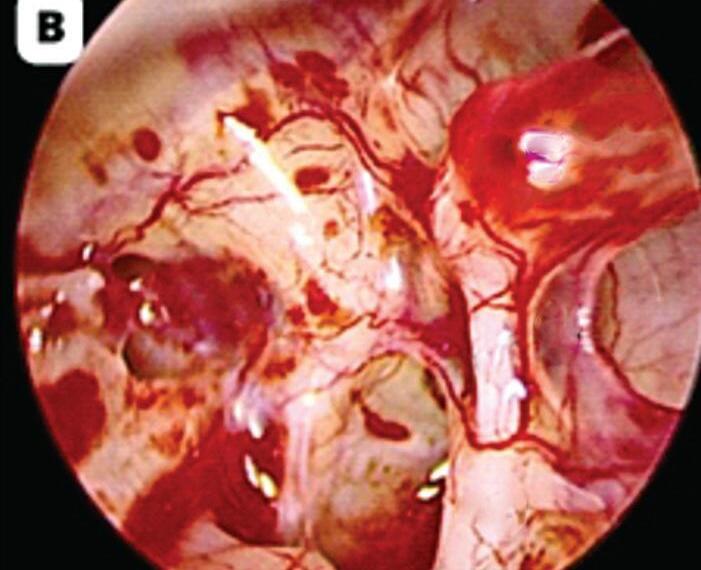

d) Os endoscópios de 0° têm uma visão reta e geralmente são usados no início das cirurgias e ficam na porção posterior do meato acústico (Fig. 1-2a); os de 30° devem ficar na porção mais inferior do meato acústico externo para permitir uma visão mais adequada do ático e do antro (Fig. 1-2b).

Fig. 1-2. Visualização endoscópica da orelha média esquerda com ópticas de angulações diferentes.

(a) 0°. (b) 30°. (c) 45°. (d) 70°. EMP, eminência piramidal; NJR, nicho janela redonda; NF, nervo facial; P, promontório; PL, platina; TTE, tendão tensor do tímpano.